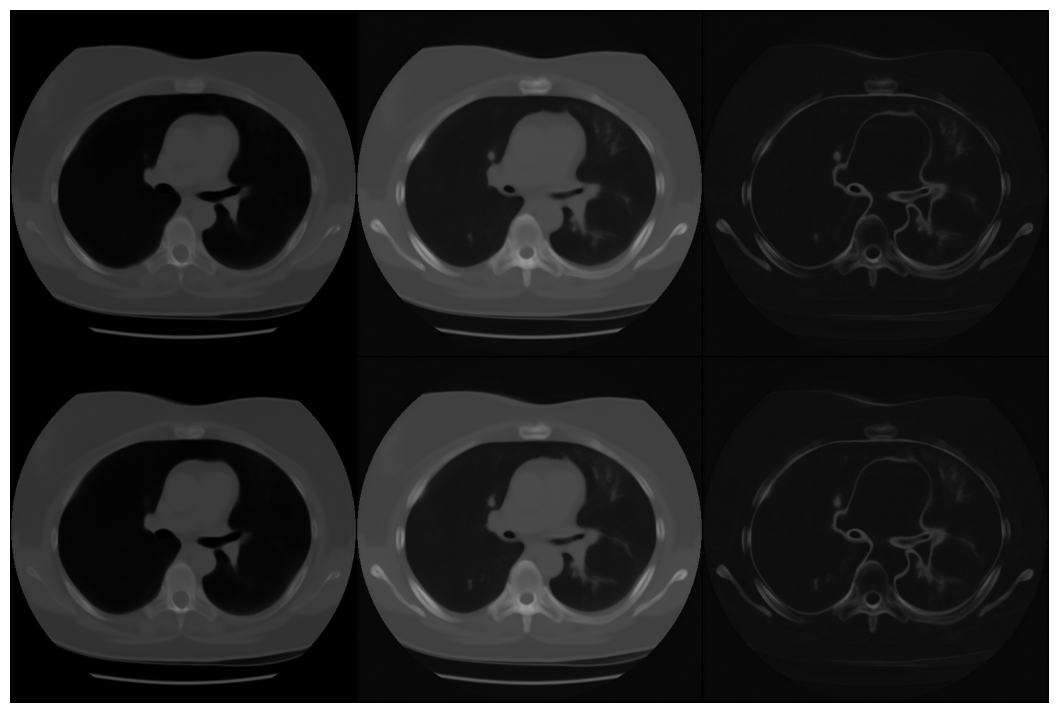

Conditional Samples (Poisson vs Gaussian DPS)

Poisson

Gaussian